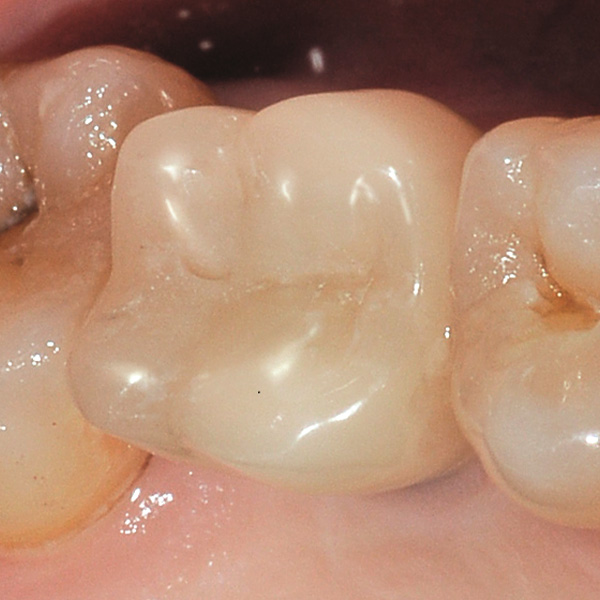

Restorations and implants are exposed to especially high loads. After extraction and implantation, the patient lacks the elastic fiber apparatus of the natural dental bed. As a result, chewing forces are not absorbed, but transmitted directly to the restoration, the implant, the bone and the opposing dentition. The hybrid ceramic VITA ENAMIC provides a dual network structure of ceramic (86 wt%) and polymer (14 wt%). This results in a dentin-like elasticity and the ability to absorb chewing forces. Due to its high vertical dimension, the polychrome blank VITA ENAMIC multiColor in the EMC-16 geometry enables the production of one-piece, monolithic abutment crowns, even with atrophied bone. In the following article, dentist Professor Dr. Alexander Hassel demonstrates how he provides a patient with this type of restoration.